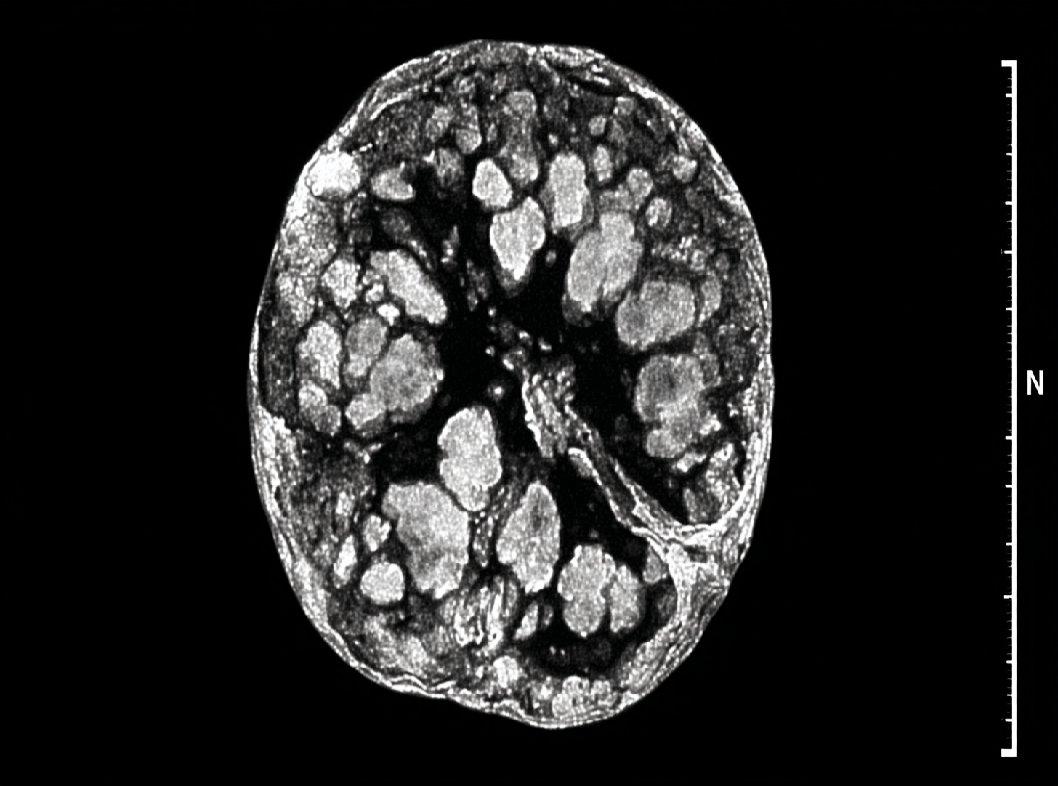

- Импульсивная томография гипофиза (МРТ): Это изображение гипофиза с использованием магнитного резонанса. МРТ позволяет врачам визуализировать опухоль и определить ее размер, форму и точное местонахождение.

Компьютерная томография (КТ) гипофиза: В редких случаях, когда МРТ недоступна или нецелесообразна, может быть применена КТ для дополнительной визуализации. - Рентген головного мозга (турецкое седло): Это рентгенологическое исследование для оценки состояния турецкого седла, в котором расположен гипофиз.